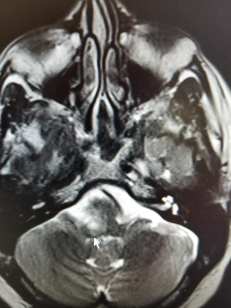

Dr. Flanagan arrives a few minutes after the assistant leaves, and begins to review BJ’s records. After talking with BJ at length about his symptoms, he has BJ go through a series of examinations to evaluate his vision, balance, reflexes and strength. He tells BJ that he is leaning towards an initial diagnosis of MS and proceeds to show us the lesions on one of BJ’s brain scans that lead him to this conclusion. BJ

’s lesions are a-typical for MS which is why he was unable to get a diagnosis, even after visiting John’s Hopkins in Baltimore. Dr. Flanagan shows us a recent clinical paper regarding lesions similar to BJ’s that have proven to be MS related.

Our appointment with Dr. Flannagan confirmed what he had thought in the beginning. BJ was officially diagnosed with reoccurring/relapsing MS. His a-typical lesions made the diagnosis difficult, but the doctor was convinced based on the results of his latest MRI, a review of a previous spinal tap, and his symptoms.